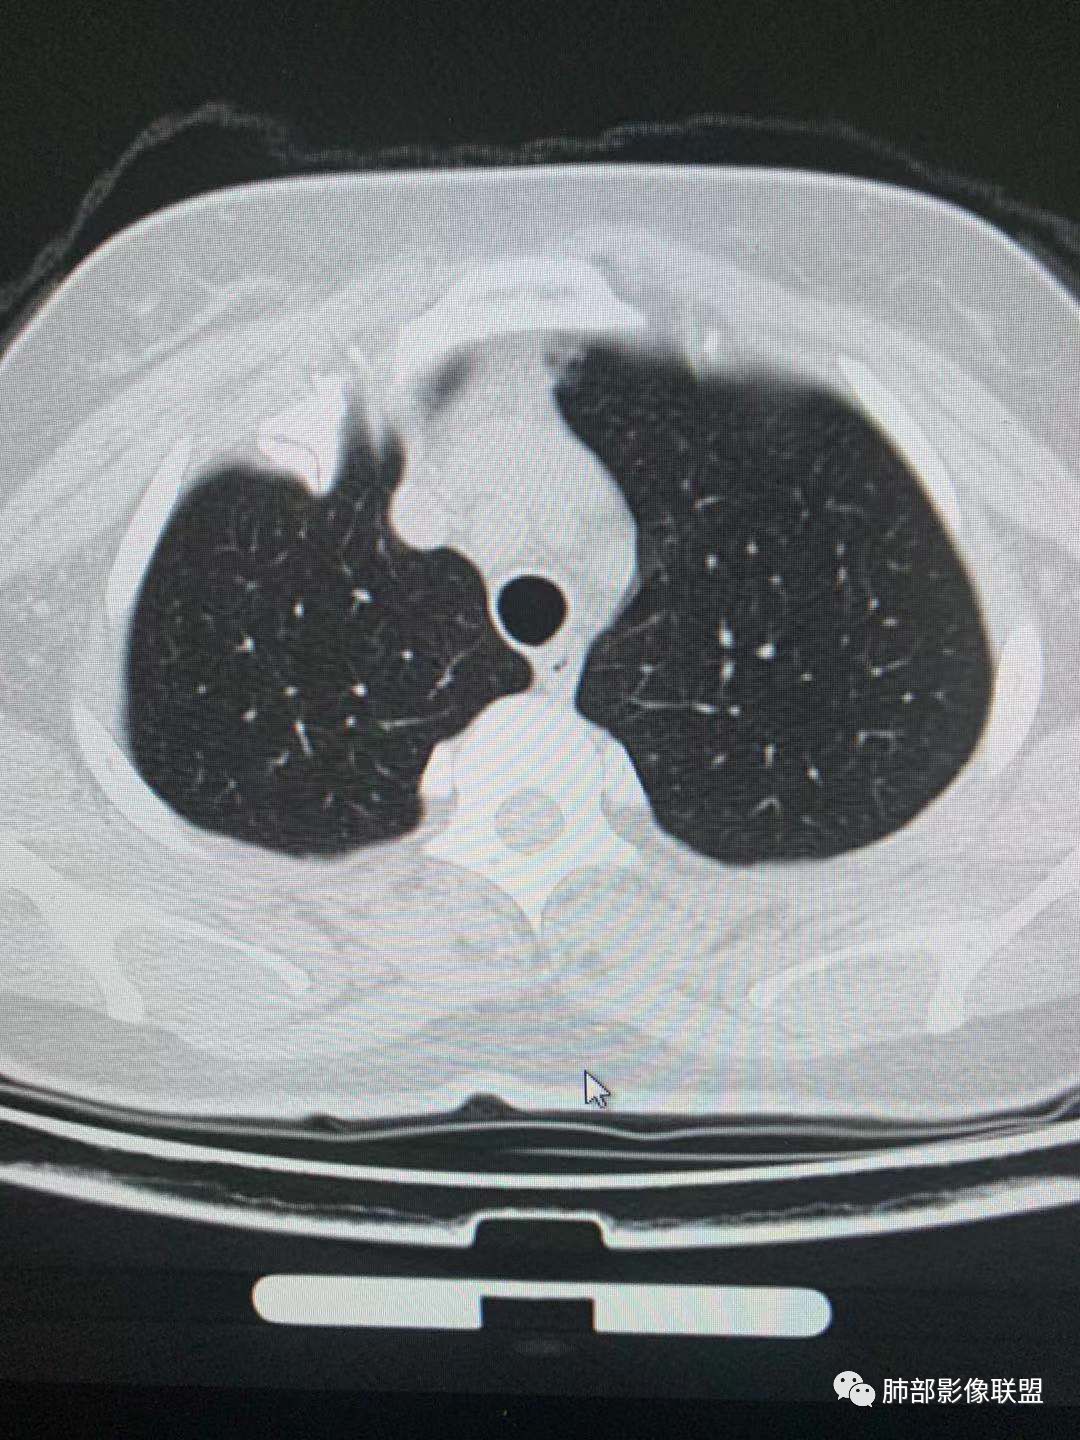

中年女性,体检发现。胸部CT示左肺上叶尖后段结节,边界清楚,边缘无分叶,邻近支气管无受压及阻塞;纵膈窗显示结节密度均匀,增强扫描中度渐进性均匀强化,未见坏死及空洞,考虑良性。结节周围可见磨玻璃晕征,并见血管贴边征,考虑硬化性肺细胞瘤(PSP)。

左肺上叶前段可见一磨玻璃结节,边界清,可见小叶间隔阻挡、毛刺 、胸膜牵拉,考虑微浸润腺癌。左肺上叶尖后段可见一实性结节影,边缘光整,光滑浅分叶,周围可见晕征,增强扫描明显延迟强化,可见血管贴边征,结节内未见气管及血管影,女性,考虑PSP

傅昌瑜

45岁女性,无症状。CT:左上叶前段见一小磨玻璃结节,边请,似有毛刺,边缘见月芽铲,考虑AIS→MIC可能;左上叶尖后段见一圆形实性结节,边清,无分叶,见血管及支气管贴边,增强后延迟强化,考虑良性结节,PSP可能性大,稍不放心的地方局部边缘见边界清楚的磨玻璃影,注意鉴别恶性肿瘤。

一.尖后段高密度大结节:

1.左肺上叶尖后段较大类圆形实性密度结节影,密度均匀,中等程度强化。

2.实性密度区边缘相当清楚,表面欠光整,偶见毛刺、棘突和旁出血管结构,未见典型的深分叶及邻近胸膜凹陷。

3.可疑支气管进入受阻。可惜缺乏连贯图像或冠矢状位以资判断。

4.病灶与胸膜之间有连线,邻近段支气管及肺血管整体后移,提示病灶还是有一定收缩性。

如上,单就这实性结节,硬化性肺细胞瘤(PSP)和腺癌似乎都能够解释,形态太规整了一些。

5.病灶周围见边界清楚的磨玻璃影,有点醒目,有点意外!

这是无论如何不能忽视的征象!

这点强烈提示,要么整个病灶恶性(腺癌),要么良性病灶旁滋生恶性病灶。

两年前左上肺的病灶什么位置,什么模样,是否相关?我们不得而知。